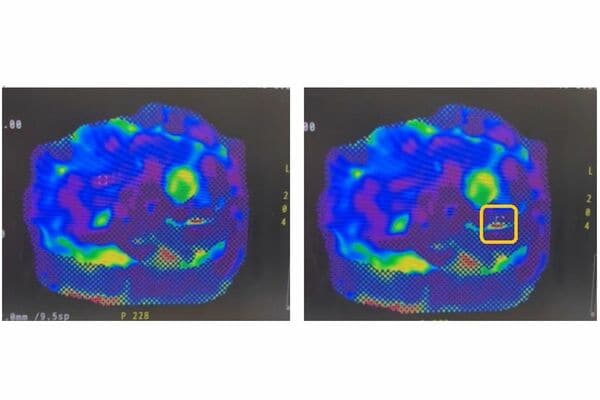

今城 硬い部分は赤く、柔らかい部分は青く画像処理されます。小さく写っていますが、もともと正常でも硬い臓器の脾臓は、赤く写ります。坂元さんの肝臓は、ほとんどが青いので、柔らかく正常な状態です。他のデータと合わせても、脂肪肝や肝硬変ではありませんね。

筆者の肝臓は青かった。右の黄色で囲った部分が実質臓器の脾臓